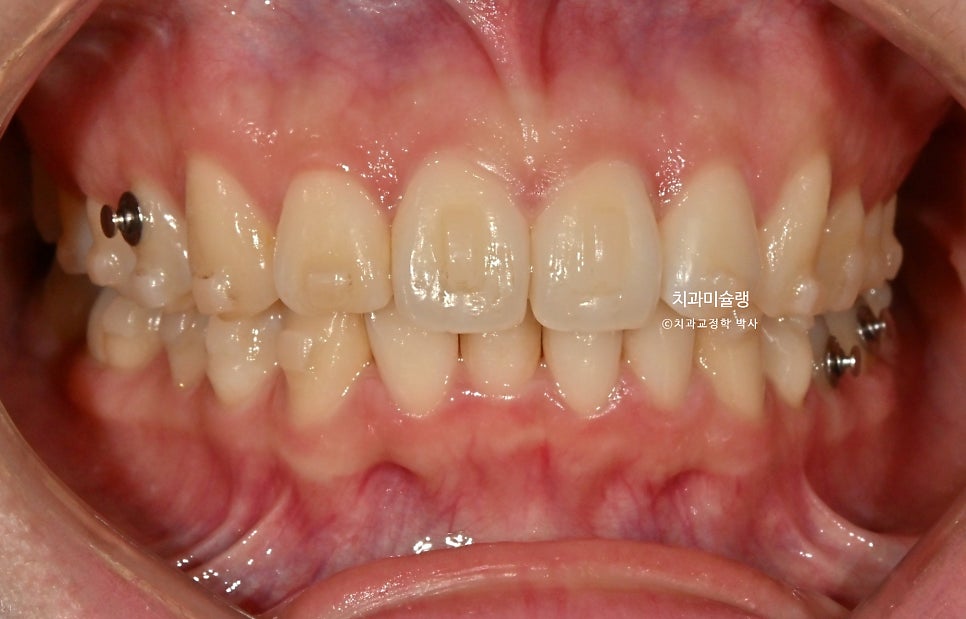

초진 상태 – 2025년 여름

2025년 여름, 앞니 부분교정을 하고싶어 온 환자분 입니다.

중심선 불일치가 보이며 아랫니가 거의 안보일 정도의 과개교합 입니다.

윗니중 가운데 앞니가 튀어나와있습니다.

환자분은 단순 앞니 배열을 생각하고 오셨지만, 앞니가 깊게 물리는 과개교합은 앞니 부분교정으로는 개선이 되지 않죠.

25년 6월부터 10월까지, 3개월 반에 걸쳐 14개 장치를 모두 낀 후 모습입니다.

과개교합이, 중심선, 배열의 개선이 보입니다.

어금니 교합은 1급 교합관계를 보이며

여기 저기 붙어있는 금속 고리의 정체는 좀전에 언급한 작은어금니 회전을 위한 부가장치 입니다.